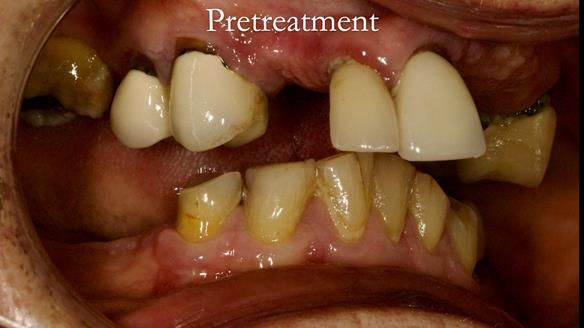

Aesthetically and functionally poor RPDs were replaced for Eileen, a 74 year old woman.

Referred to me by her general dental practitioner specifically for replacement RPDs.

Diagnoses

- Missing teeth in the upper and lower jaws

- Upper and lower metal based RPDs, poorly fitting, worn occlusal surface, reverse curve aesthetics, lacking support

- Poor dental appearance with reverse incisal curve

- The upper right central and lateral incisors with post crowns. Healthy and functionally secure but with poor appearance, contributing to the reverse curve.

- Moderate to heavily restored dentition with deep overbite (Class 2 div II)

- Yellowish lower front teeth with small amount of wear.

- The lower right canine (LR3) is worn with MOD cavity.